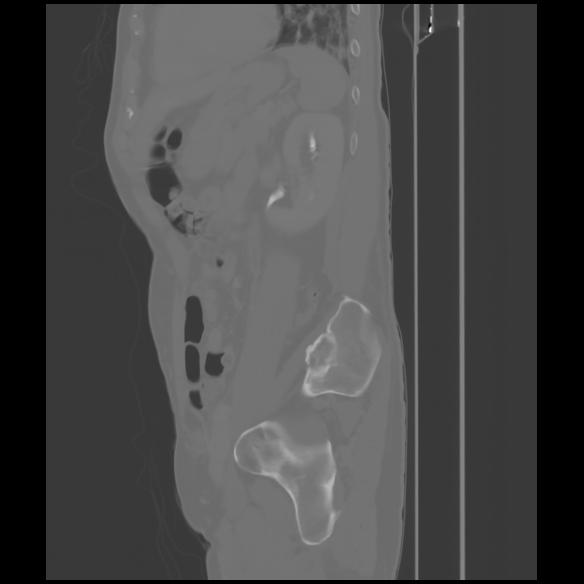

7 CUERPO,CE,Sagittal,3.000,CUERPO,Sagittal,